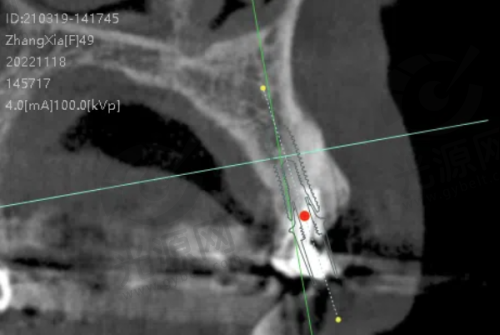

唐山地区的种植牙技术近年来不断更新,尤其是数字化种植技术和微创种植技术逐渐开始普及。这能有效降低患者的手术风险和修复时间,提高成功几率。